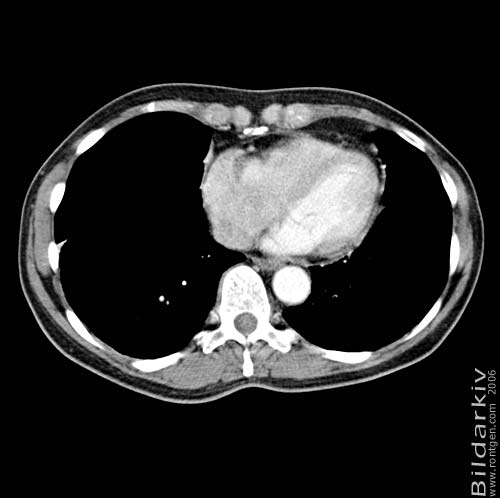

Thorax 42

Snitt över thorax med kontrast. Sk. mediastinum-fönstersättning.

CT Röntgen Helsingborgs lasarett

Mediastinum